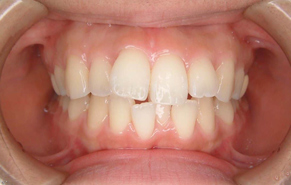

前歯のガタガタと口元の突出感を改善したいと言われました。

口元の突出感の改善には抜歯が必要となり、上下左右の計4本を抜歯しています。治療後は抜歯した隙間を使って配列して、閉じることで口元を入れました。